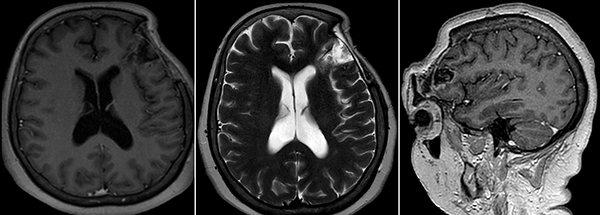

Figura 2. RM de cerebro. A) Secuencia T1 sin contraste endovenoso. B) y C) Secuencia T1 con contraste endovenoso. D) Secuencia T2.

Resonancia magnética (RM) de encéfalo con contraste endovenoso evidenció una lesión heterogénea, predominantemente hipointensa en secuencia T1, hiperintensa en T2, heterogénea e isointensa con respecto al parénquima cerebral en Flair (Fluid attenuated inversión recovery), con escasas áreas de restricción en la secuencia difusión (DWI) y realce fino periférico tras la administración de contraste (Figura 2). Se observó efecto de masa leve con colapso de asta frontal de ventrículo lateral homolateral. Se realizó una angiotomografía de encéfalo para valorar la vascularización adyacente de la masa y descartar anomalías vasculares, siendo negativa para las mismas.